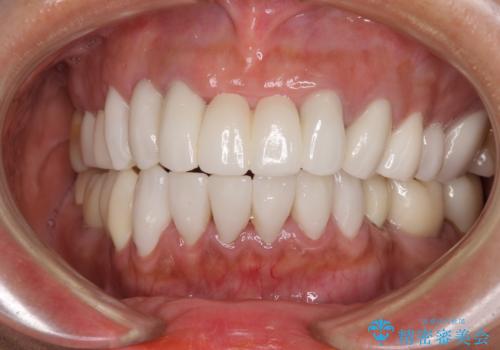

抜歯が必要な左右の奥歯 ブリッジとインプラントによる奥歯の補綴治療

![[ 欠損補綴 ] ブリッジとインプラントの症例 治療前](https://seimitsushinbi.jp/wp/wp-content/uploads/2021/10/d680d397e015686572db595995781e12-500x350.jpg?v=1634192539)

![[ 欠損補綴 ] ブリッジとインプラントの症例 治療後](https://seimitsushinbi.jp/wp/wp-content/uploads/2021/10/82c7cc111177152f4f990e0f169487f7-500x350.jpg?v=1634192579)